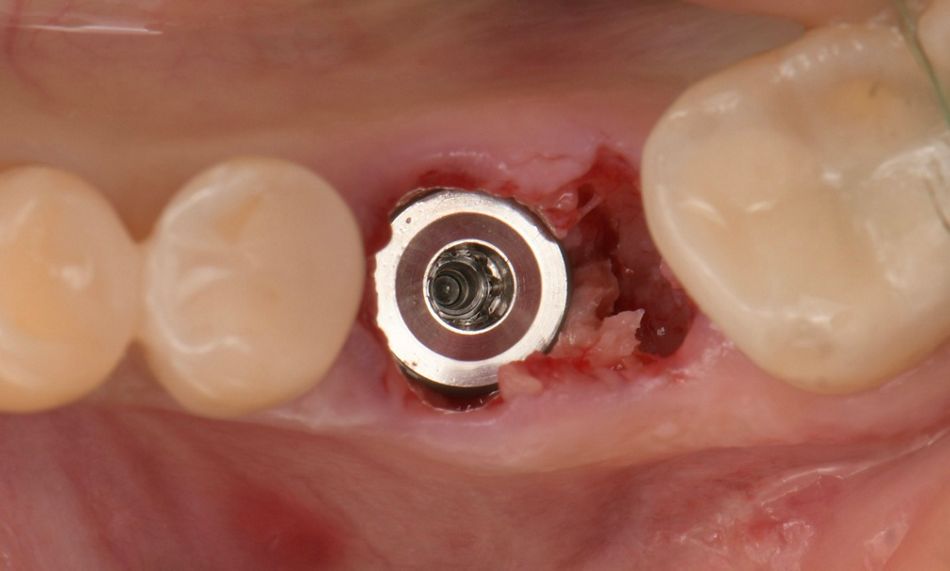

Intraoral examination revealed a root remnant of tooth #36, previously endodontically treated, showing secondary caries and a Grade III furcation involvement (Fig. 1).

Fig. 1

The patient was prepared following standard clinical protocols, and local anesthesia was administered using Ubistesin®. Tooth #36 was atraumatically extracted. After extraction, the site was prepared for implant placement by performing an osteotomy according to the manufacturer’s recommendations. A Straumann BLC™ Ø 6.5 × 6 mm SLActive® Roxolid® implant was immediately placed in the extraction socket using a flapless, non-submerged approach. The implant was placed free-hand, with careful attention to buccolingual and mesiodistal alignment. The orientation dots on the implant driver were positioned in the buccolingual direction to ensure proper positioning. Primary stability was achieved with an insertion torque of 35 Ncm (Fig. 3).

Fig. 3